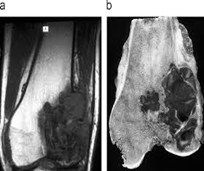

Se usa una amplia gama de técnicas de adquisición de imágenes para poder ver dentro del cuerpo y determinar el alcance de un sarcoma óseo y establecer la presencia o ausencia de enfermedad metastásica distante.

1. Rayos X

2. Resonancia magnética

3. TAC contrastado

4. Gammagrafía Ósea

Examen histopatológico

El examen histopatológico, es decir, el examen de tejidos en un microscopio, se lleva a cabo sobre una biopsia o porción de tejido tras la extirpación de todo el tumor por cirugía. Sólo la evaluación histopatológica del tumor revelará si el tumor es un sarcoma óseo y, en su caso, de qué tipo. También proporcionará el “grado de malignidad”, esto es, una clasificación de la agresividad de las células del cáncer.